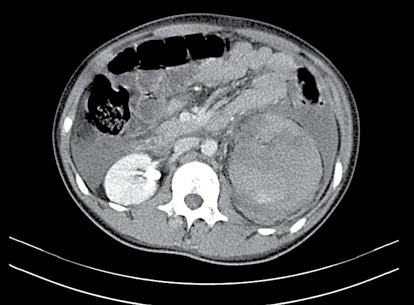

Paciente, vítima de acidente de moto, atendido pelo SAMU, chegou ao pronto-socorro de hospital terciário, consciente, queixando-se de dor na região lombar e flanco esquerdo. Tinha recebido previamente 1 000 mL de Ringer-lactato. Ao exame, mucosas pouco descoradas, sem cianose, PA: 130/80 mm/Hg, FC: 96/min., rítmico. Abdome não distendido, doloroso no flanco e região lombar esquerda com hematoma superficial e escoriações no local. A sondagem vesical realizada sem dificuldades apresentou 150 mL de urina “concentrada”. Permaneceu em observação e, devido às condições hemodinâmicas estáveis foi submetido à tomografia computorizada abdominal.

enunciado 925164-1

Diante da imagem apresentada e do contexto anterior, pode- se afirmar que se trata de: